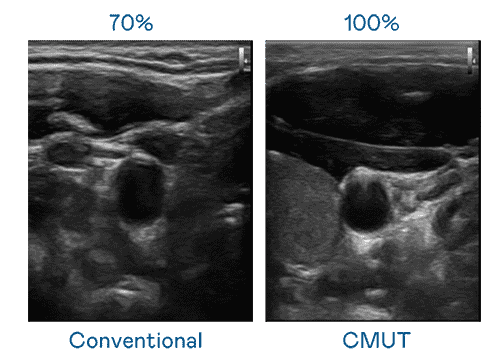

CMUT 技术是一种用电容式微机电元件来产生超音波讯号的技术。。与传统 PZT 压电式技术相比,,CMUT 频宽增加 30%,,,更宽频的超音波讯号让影像解析度大幅提升,,是实现高影像品质医疗超音波扫描、、、促进精准医疗发展的关键技术。。。

大频宽带来超清晰影像

超音波影像的解析度高低,,,,首先取决于探头能发出的讯号频宽。。。。优游UB8 CMUT 可提供高清晰的超音波讯号,,,提供高频宽、、、高灵敏度、、影像纹理细节更高的超音波影像,,协助医护人员缩短影像判读时间及利用精准的医疗影像进行诊断。。。。